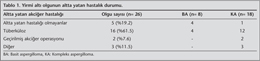

Altta Yatan Akci?er Hastal???

Olgular?n 5 (%19.2)'inde herhangi bir altta yatan hastal?k yok iken, 16 (%61.5) olguda t?berk?loz hikayesi, 2 (%7.6) olguda? daha ?nceden ge?irilmi? akci?er operasyonu (bir olguda aspergilloma, bir olguda akci?er kist hidati?i nedeniyle), 1 (%3.8) olguda bron?ektazi ve 1 (%3.8) olguda b?ll?z akci?er mevcuttu. Bir (%3.8) olgu l?semi nedeniyle kemoterapi almaktayd? (Tablo 1). Kemoterapi almakta olan olgu dahil hi?bir olgunun imm?n depresyonu bulunmamaktayd?.? Altta yatan hastal??? olmayan olgular?n istatistiksel olarak basit aspergillomal? grupta daha fazla oldu?u saptand? (p= 0.02).

Radyolojik Bulgular ve Tan?

Belcher ve Plummer'?n radyolojik s?n?fland?rmas? g?z ?n?ne al?narak yap?lan s?n?fland?rmada 8 (%30) olgu? basit, 18 (%70) olgu kompleks aspergilloma olarak belirlendi (9) (Tablo 2). On yedi olgunun preoperatif aspergilloma tan?s? radyolojik g?r?n?mlerindeki karakteristik yar?m ay ?eklinde radyol?sens alanla ?evrili mantar topu (Monad's sign) g?z ?n?ne al?narak konmu?tu. Geriye kalan dokuz olgunun tan?s? patoloji piyesiyle konuldu. Bu olgular?n ??? masif hemoptizi nedeniyle opere edilen, ??? semptomu olmay?p eksplorasyon uygulanan, ??? de ba?ka tan?larla (biri haraplanm?? akci?er, biri bron?ektazi, biri de skuam?z h?creli akci?er karsinomu) operasyona al?nan olgulard?.